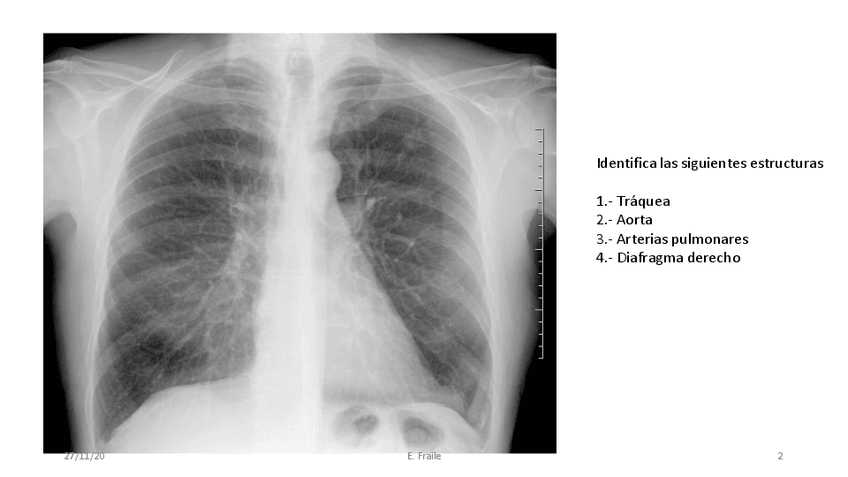

He publicado nuevos apuntes de 2º Anatomía II: ECOGRAFIA-EN-ANATOMIA.pdf

2 páginas